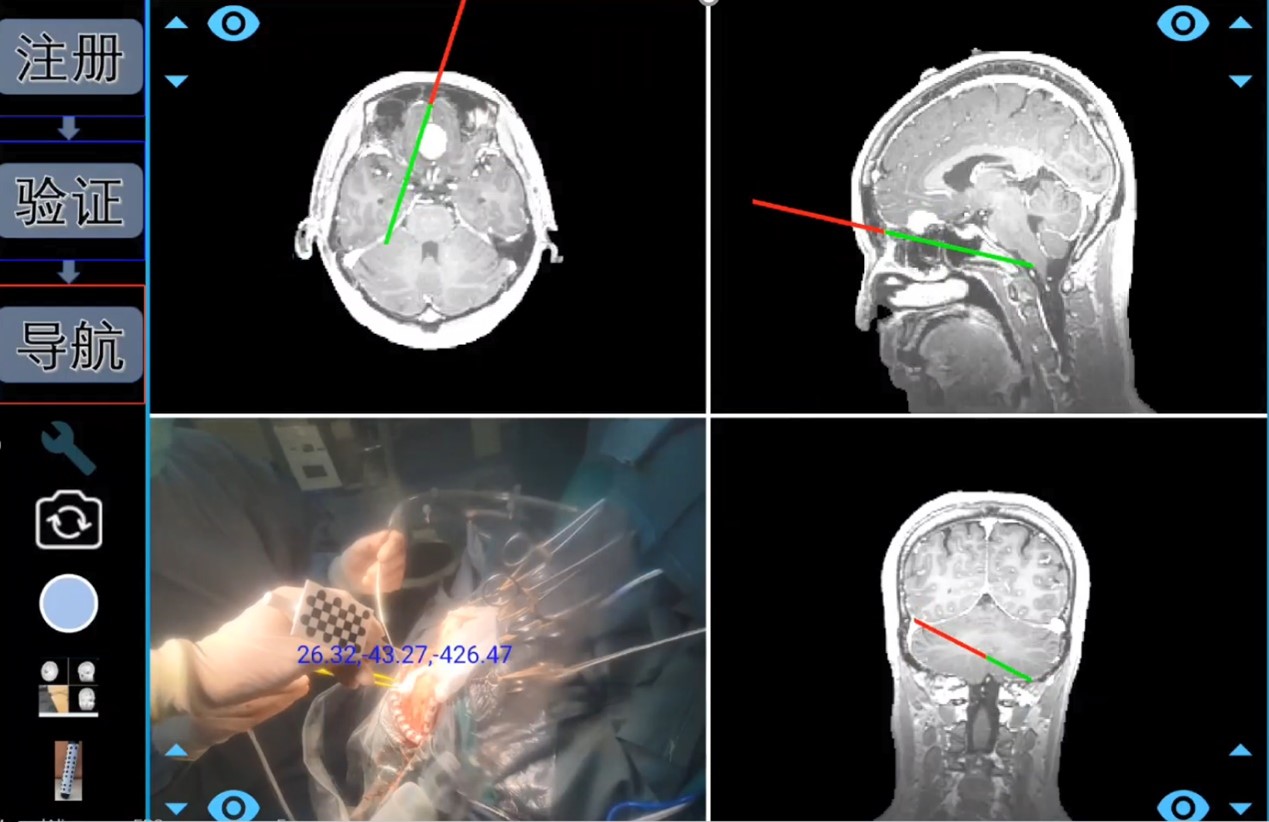

(手术导航术中使用场景&系统核心组件)

整个系统集光学定位和SLAM跟踪于一体,通过光学定位,该手术导航系统能实时跟踪手术器械;通过实时定位技术(SLAM),系统可在无需头架和参考架的情况下,多角度观察病灶位置。

借助深度相机,综合深度学习和视觉算法,该系统能实现虚拟空间和现实空间的高精度一键配准,将生成的3D“透明脑”1:1与病人实际情况进行匹配, 进行术中导航。

(术中导航)

试验数据显示,其配准精度可达亚毫米级。算法能力的提升,可将传统手术导航的配准时间由传统的近半个小时,缩短至几秒钟,为病人抢占宝贵的治疗时机。